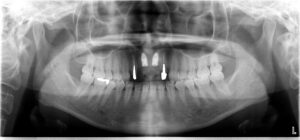

前歯が折れています。患者さんは義歯やブリッジよりインプラントを選択されました。

インプラントを埋入。